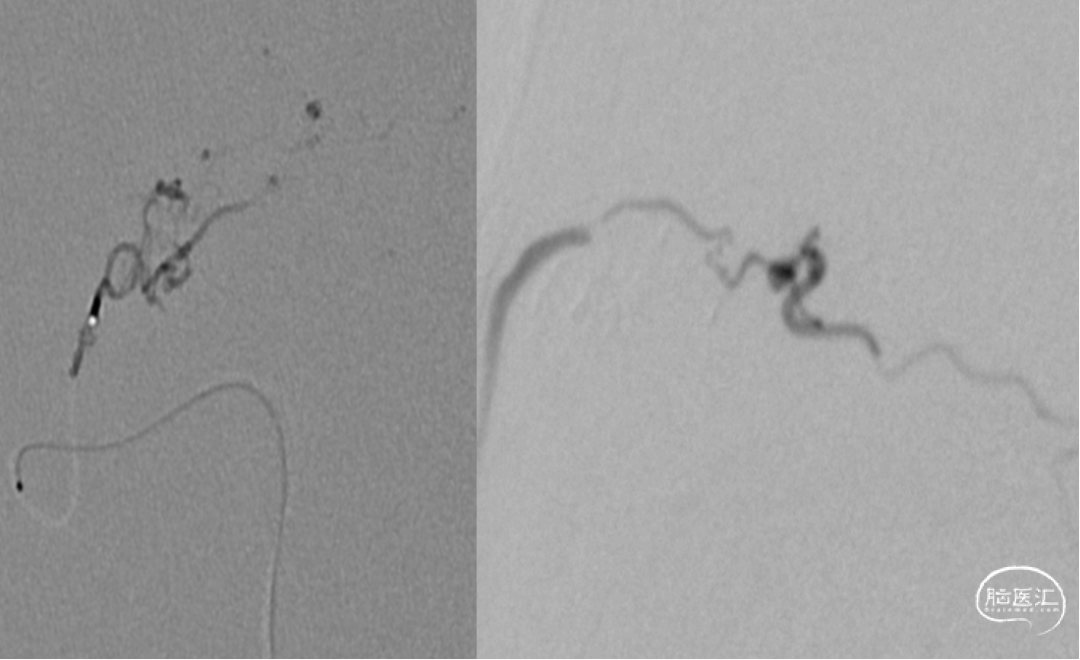

术后即刻造影血管畸形消失

CBCT:无出血,术后无明显不适

术后4个月复查DSA血管畸形无复发